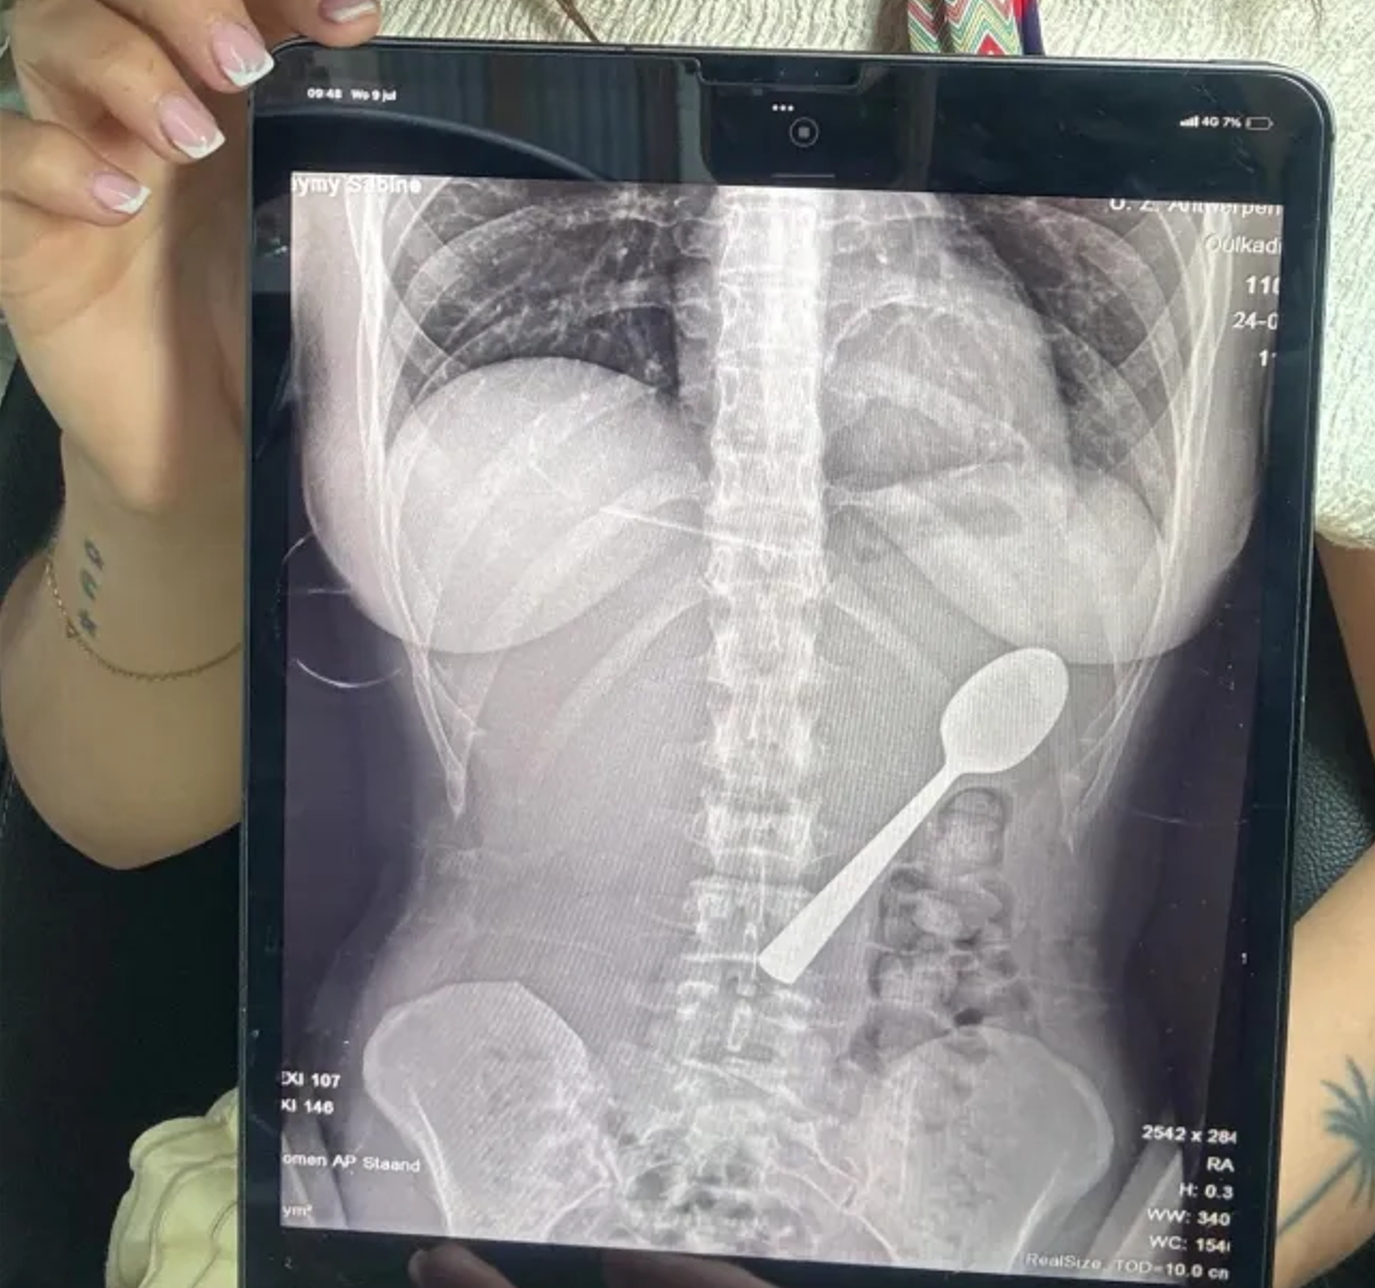

比利時一名女子日前因意外吞下長達17公分的湯匙,送醫取出!據英媒《地鐵報》報導 ,28歲的愛美林克斯(Reymy Amelinckx)在家中吃優格時,因飼養的匈牙利維茲拉犬馬利(Marley)突然跳上身體而受驚,導致17公分的湯匙卡進喉嚨,最後只能吞下。

醫師檢查後指出,湯匙尺寸過大,不可能自然排出,於是為愛美林克斯安排兩天後的胃鏡手術。愛美林克斯當天只得回家等候,兩天期間仍明顯感覺到湯匙在體內移動。醫療團隊在兩天後為愛美林克斯進行局部麻醉、才總算將湯匙旋轉並取出,過程中雖有輕微胃部出血與食道損傷,但好在後續恢復情況良好。